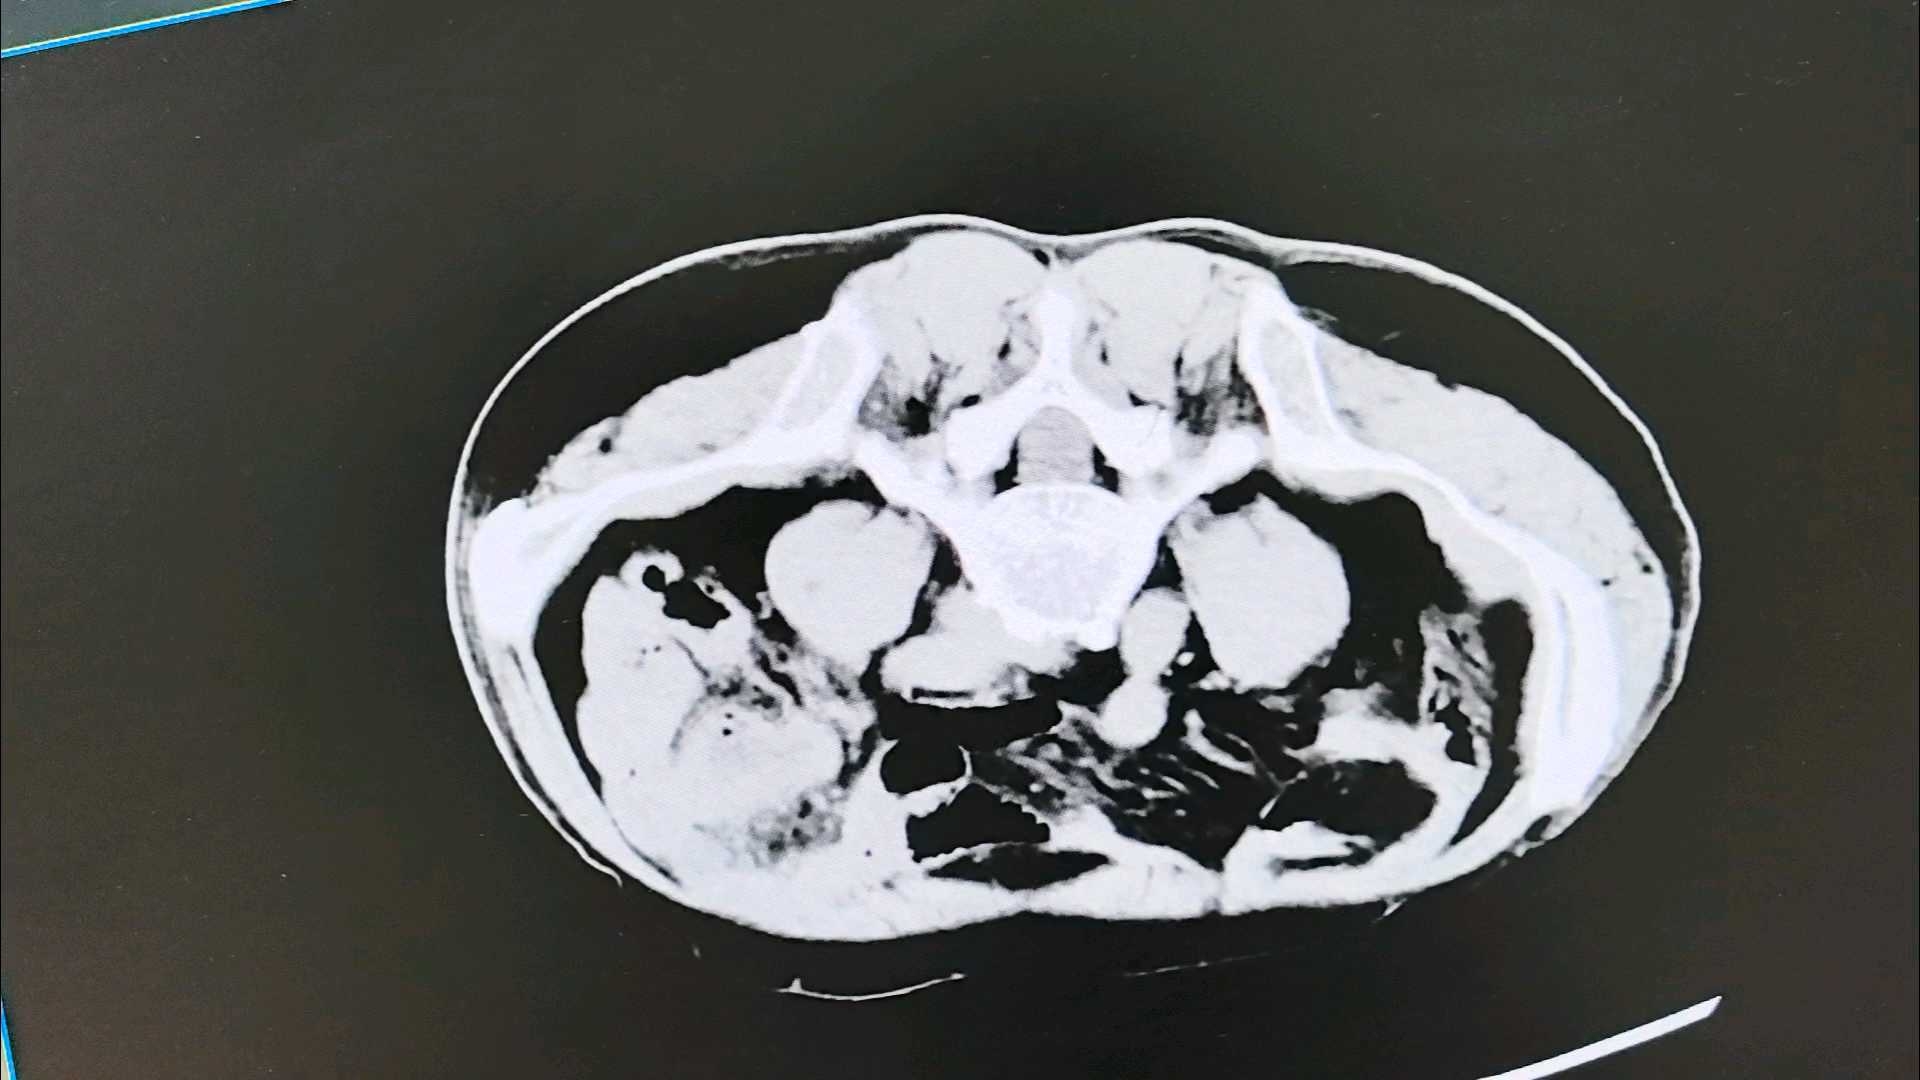

1、入院时急诊CT片(会阴木棍嵌顿,不能平卧,是个特殊的俯卧位拍片。)

临床读片:木棍从直肠侧后方刺入。拍片距离受伤时间有10小时。直肠周围清晰,伤口无活动性出血。